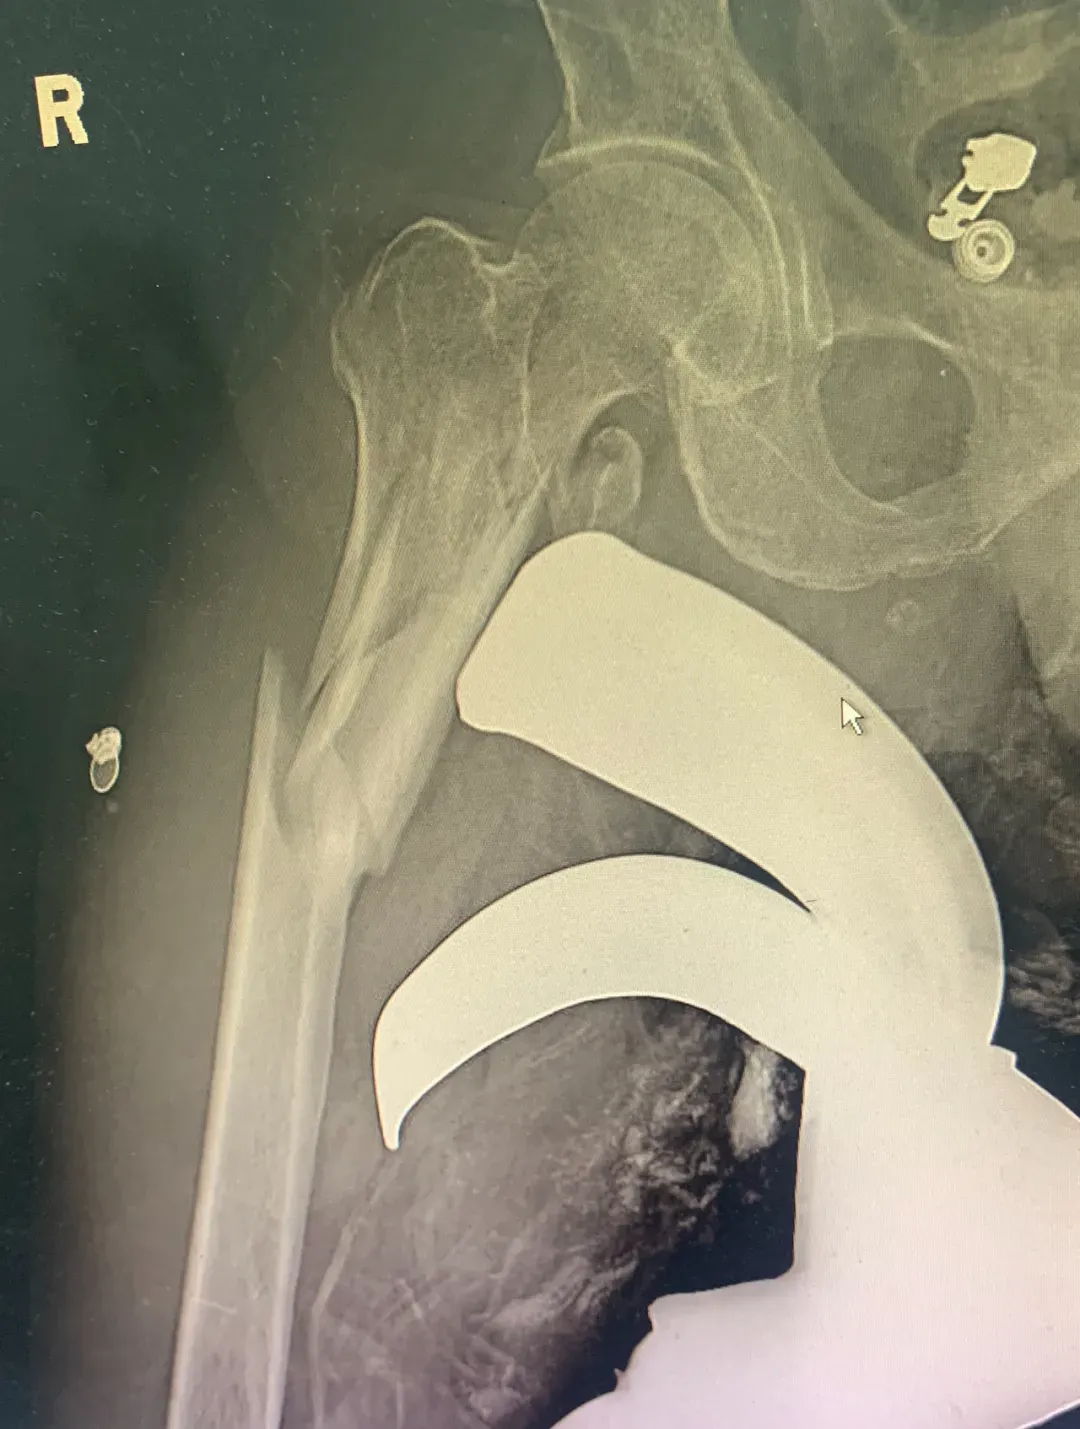

医院立即启动危重创伤救治绿色通道。手足外科马阳副主任医师紧急会诊,患者被迅速收治入院。在手足外科管英杰主任的带领下,手足外科团队争分夺秒地进行术前准备。X线检查结果触目惊心:右侧股骨颈、股骨干粉碎性骨折,金属异物深嵌至股骨骨折处,伤势复杂且严重。于是运动医学科庞军主任紧急加入会诊。

稳固骨架,重建支撑:运动医学科庞军主任与手足外科马阳医生联手,凭借精湛的技术,对粉碎的股骨颈和股骨干进行了可靠的复位与固定,为后续血管修复重建了稳定的骨骼框架。